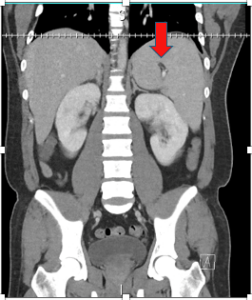

MurineTyphus_2

By Jed Henson | on February 19, 2025 | 0 Comment